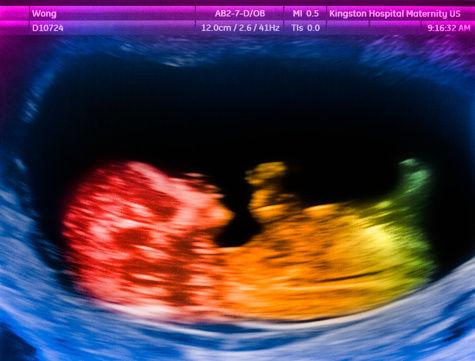

90年代国外的研究者们就通过超声波成像发现16周大的男性胎儿有勃起反应(Haffner, 1999; Martinson, 1994; Parrot, 1994)。《美国妇产科学杂志》也曾记录了一位女性胎儿自慰的全部过程,研究者看到一个32周的女性胎儿用右手手指触摸外阴,主要是集中在抚摸阴蒂的区域。这一活动持续了30-40秒,过了一段时间又再次开始,并伴随着骨盆和双腿的活动。在之后,胎儿的躯干和四肢的肌肉呈现出达到高潮的肌肉痉挛,最终放松休息,这一过程持续了近20分钟。